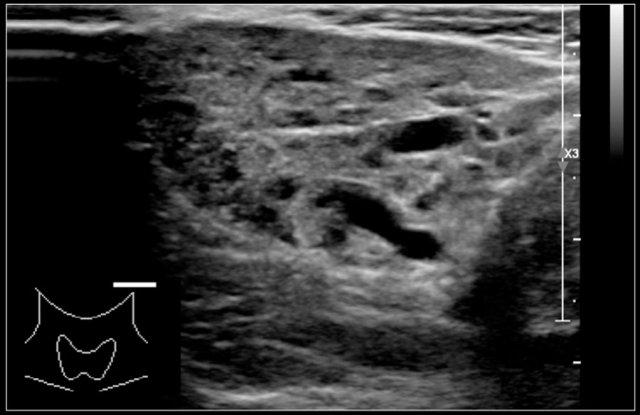

Hashimoto’s thyroiditis: An enlarged thyroid gland with a diffuse inhomogeneous structure and hyperemia is seen in a ten-year-old girl

Các dạng viêm tuyến giáp phổ biến nhất là viêm tuyến giáp Hashimoto và bệnh Graves.

Cả viêm tuyến giáp Hashimoto và bệnh Graves đều có thể biểu hiện là tuyến giáp to và tăng sinh mạch máu.

Viêm tuyến giáp Hashimoto hay viêm tuyến giáp lympho bào mạn tính là một bệnh tự miễn.

Bệnh biểu hiện với suy giáp.

Mặc dù chủ yếu là bệnh của người trung niên nhưng cũng có thể gặp ở trẻ em.

Trên siêu âm, tuyến giáp to lan tỏa và không đồng nhất.

Trên siêu âm Doppler màu, lưu lượng máu thường bình thường nhưng có thể tăng như trong bệnh Graves.

Ở giai đoạn muộn hơn, tuyến giáp teo nhỏ lại.